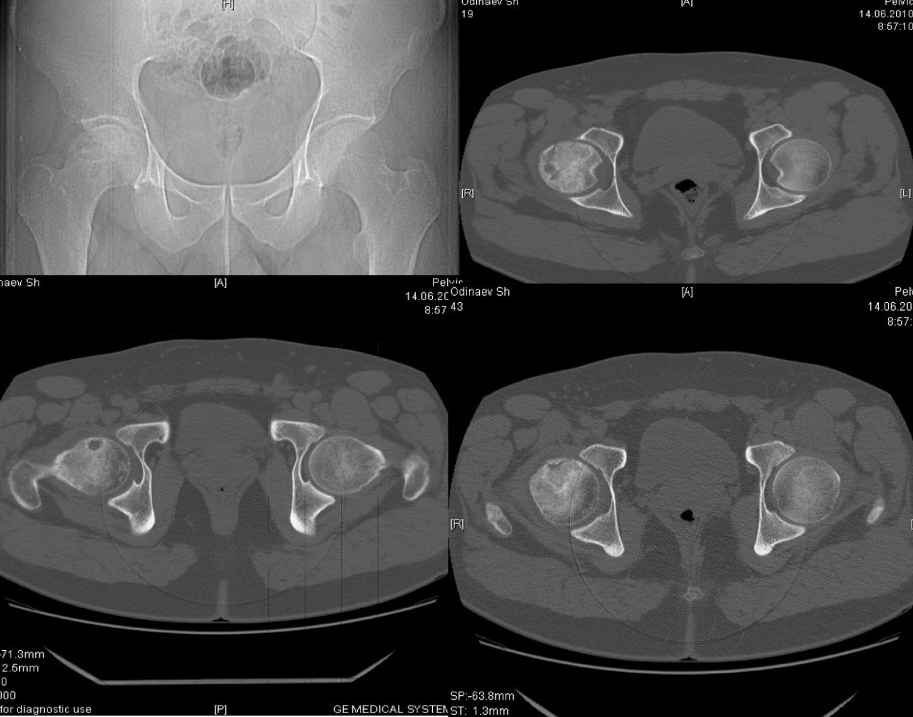

доброго времени суток уважаемые коллеги.Обратился пациент,30 лет жалуется на боли в области правого т/бедренного сустава, хромоту.

При внутренней ротации болезнгенность.Болеет в течении 3 мес. Снимки во вложении. Больной получает курс консервативной терапии. Из хондропротекторов ДОНА порошок.Хотелось бы услышать мнение уважаемого сообшесва по поводу консервативной терапии, может у кого из Вас имеется опыт по консервативной терапии с применением более эфективной медикаментозной терапии.что касается эндопротезирования мы считаем, что в таком возрасте показания относительные.Спасибо.

По представленному- головка вовлечена почти полностью в стадии импрессионного перелома (хотелось бы больше сканов). Маловероятно таблетками вырастить новую головку. Какие абсолютные показания к эндопротезированию в этом возрасте? Потеря головки на улице при открытом переломе шейки?

четкий очаг деструкции в головке бедра. возможно, имеет смысл уточнить этиологию этого процесса, т.к. при некоторых состояниях консервативная терапия противопоказана. сцинтиграфия? (желательно 3-х фазная)

Для меня не хватает информации о начале задолевания и объективном статусе. А не опухоль ли это???

абсолютно не разумеется, перечисленные вами методики работают от стадии сегментарного некроза (туннелизации, Core decompression) до стадии сегментарного коллапса ( варианты корригирующих остеотомий, например ротационная) проблема в том, что здесь похоже некроз субтотальный (нужно больше сканов)с импрессионным переломом.